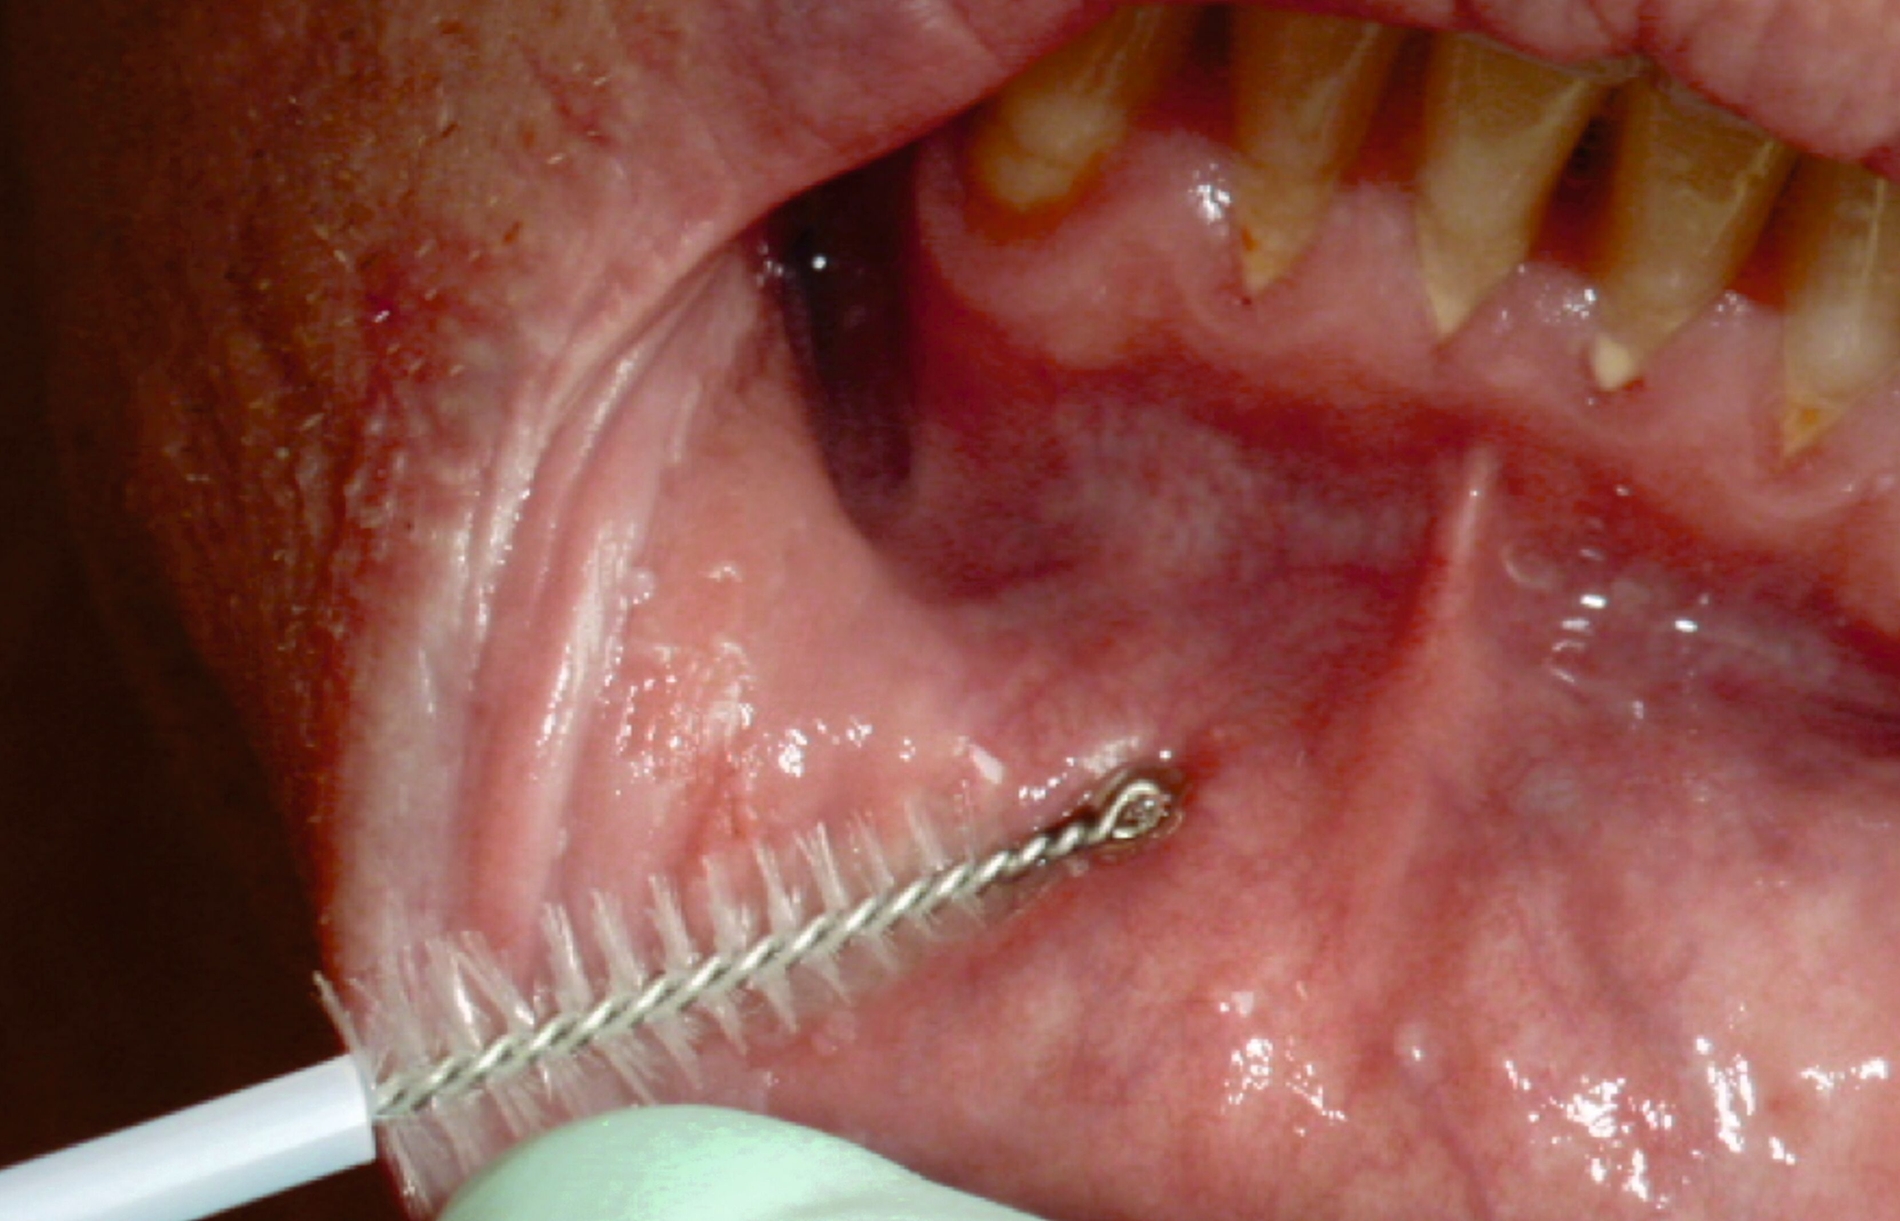

Da jedoch unklare Mundschleimhautveränderungen, deren überwiegender Anteil harmlos ist, bei bis zu 25 Prozent der Bevölkerung beobachtet werden können, wären Skalpellbiopsien auf breiter Front nicht nur unverhältnismäßig, sondern auch unrealistisch [Kämmerer et al., 2017]. Zur Diagnostik und zur Verlaufskontrolle malignitätsunverdächtiger OLP-Läsionen (geringes Entartungsrisiko) eignet sich in der Zahnarztpraxis insbesondere die wenig-invasive Bürstenbiopsie [Kämmerer et al., 2013], während andere visuelle Systeme momentan noch keine ausreichende Evidenz (vor allem im Sinne einer zu geringen Spezifität) aufweisen, um in der Praxisroutine zur Detektion (prä)maligner Läsionen genutzt zu werden [Kämmerer et al., 2015; Coll et al., 2022].

Bei der Bürstenbiopsie (als Bürstenabstrich von der Schleimhaut entsprechend BEMA-Pos. 05, GOZ-Pos. 6010 beziehungsweise GOÄ-Pos. Ä2002 abrechenbar; Abbildung 5) werden mit einer rigiden Bürste einzelne Zellen von der Läsion abgestrichen. Während einige Autoren die Bürstenbiopsie als äquivalent zur Skalpellbiopsie sehen [Babshet et al., 2011], zeigten andere eine – je nach dem untersuchten Kollektiv – im Vergleich zur Skalpellbiopsie niedrigere Sensitivität von 55 bis 89 Prozent und eine Spezifität von 82 bis 100 Prozent [Koch et al., 2011; Kämmerer et al., 2013].